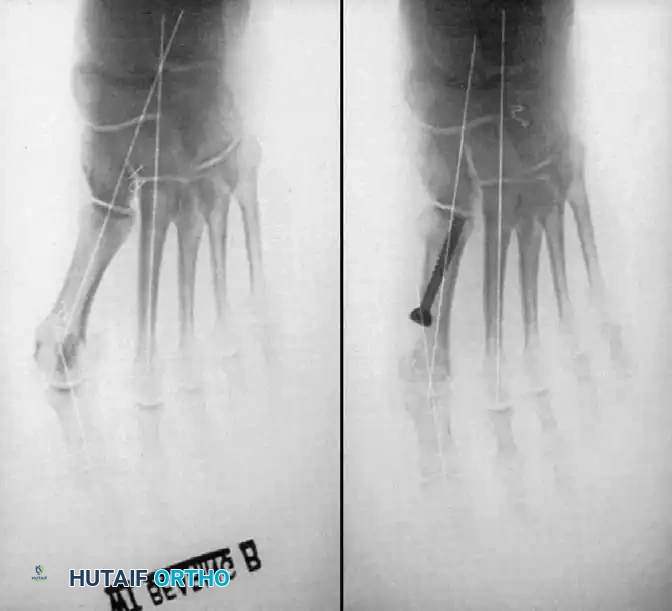

Keller Resection Arthroplasty The Keller procedure combines resection hemiarthroplasty of the fi rst metatarsophalangeal joint with removal of the medial eminence of the fi rst metatarsal (Fig. 78-28). Although removing the base of the proximal phalanx decompresses the joint and mobilizes the hallux, allowing marked correction of valgus, the varus of the fi rst metatarsal is not corrected, and maintaining correction of the valgus of the hallux is diffi cult. Other complications of the Keller procedure have been emphasized in the literature to such an extent (with neither the incidence nor the severity of such complications clearly documented) that the indications for this procedure have been limited severely. In our experience, however, complications are uncommon if patients are selected carefully. Modifi cations in the original technique also have allowed expansion of the indications for the Keller bunionectomy. Candidates for the Keller procedure are patients older than 50 years with moderate-to-severe hallux valgus (30 to 45 degrees); intermetatarsal angles of 13 degrees or less, indicating mild-to-moderate metatarsus primus varus; and pain over the medial eminence with any shoe worn, so the variety of shoes the patient can wear is severely limited. An incongruous fi rst metatarsophalangeal joint caused by

Fig. 78-26 Modifi ed McBride bunionectomy (DuVries; Mann). A, Medial capsule of second metatarsophalangeal joint is sutured to lateral capsule of fi rst metatarsophalangeal joint with interposition of released adductor hallucis. B, Medial capsular resection. C, Confi guration after capsular resection. D, After capsular imbrication, hallux should rest in neutral position or not exceed 5 degrees of varus. E, Postoperative dressing technique (Mann). ( E after Beverly Kessler; courtesy of LTI Medica and The Upjohn Company.) lateral subluxation of the phalanx on the metatarsal head, severe lateral displacement of the sesamoids, and any evidence of degenerative cartilage changes in the joint all are radiographic indications for the Keller procedure. Two modifi cations in technique can expand these indications, however, to include patients with more severe deformities (Fig. 78-29) (but not to include younger patients): fi bular sesamoidectomy and lateral displacement of the fi rst metatarsal. Using these modifi cations, Donley et al. obtained an average 18-degree correction of the metatarsophalangeal angle and an average 6-degree correction of the intermetatarsal angle in 38 patients (50 feet);

Fig. 78-28 A, Anteroposterior radiograph of right foot of 65-year-old patient shows mild-to-moderate deformity and mild degenerative changes at fi rst metatarsophalangeal joint; patient had intraarticular and periarticular symptoms. B, Twelve years after Keller procedure with excision of fi bular sesamoid; note correction of fi rst metatarsal varus and maintenance of enough joint space to allow functional range of motion.

D

Fig. 78-29 Severe hallux valgus with bursa formation in 70-year-old woman. A and B, Anteroposterior and lateral clinical photographs of patient’s right foot. C, Correction of deformity by modifi ed Keller procedure. D, Preoperative and postoperative weight bearing radiographs of same patient.